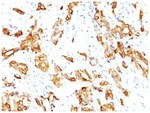

HSP27 Monoclonal specifically detects HSP27 in Human, Mouse, Rat, Chicken, Chimpanzee, Monkey, Sheep samples. It is validated for Western Blot, Flow Cytometry, Immunohistochemistry, Immunocytochemistry/Immunofluorescence, Immunohistochemistry-Paraffin.Specifications

| This MAb reacts specifically with heat shock protein HSP27 in human and monkey tissues and cell lines such as MCF-7. HSP27, also referred to as the Estrogen-Regulated 24K protein and HSP28, is one of several small heat shock proteins produced by all organisms studied. HSP27 synthesis is induced by elevated temperature, as well as by estrogen in hormone responsive cells. Interestingly, human HSP27 also shares greater than 50% homology with low molecular weight Drosophila HSPs and mammalian alpha-crystalline lens protein. Because of the estrogen responsive nature of HSP27, this protein has been studied extensively in human estrogen responsive tissues such as cervix, endometrium and breast tissue. Therefore HSP27 may be useful in classifying various hormone sensitive tumors. |